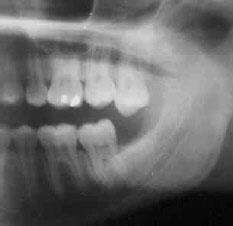

кариес корня соседнего 7-го зуба. Часто, когда 8-ка «застряла» и не имеет шансов прорезаться дальше, но и не беспокоит, пациенты и не думают обращаться к доктору, т.к. «не болит». На самом деле, такой полупрорезавшийся зуб, затрудняет нормальную гигиену в этой области и это приводит к поражению кариесом соседнего зуба. Причем самое неприятное в этом варианте то, что кариес развивается около самого основания зуба, развивается незаметно, полость долгое время может оставаться незаметной. В результате вырастает огромная «дыра», уходящая глубоко под десну, и восстановить такой дефект качественно не всегда потом возможно. Как финал – потеря хорошего соседа из-за неубранного вовремя «мудрого зуба». Причем восполнить утраченную 7-ку можно будет только имплантом (что недешево), либо съемным протезом (что неудобно в пользовании и заметно снижает качество жизни)